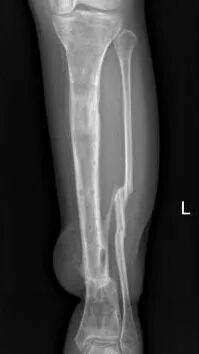

多年来,贵州航天医院各科室紧跟医学前沿,不断强技术、补短板,大力开展新技术、新项目,完成了许多高精尖、高难度、本地区“首例”的技术,填补了医院医疗技术空白,满足了群众日益增长的医疗需求。 贵州航天医院骨科率先在遵义地区开展骨搬移技术,截至目前,已治愈慢性骨髓炎、感染性骨不连、骨缺损、脉管炎、糖尿病足患者200余例,糖尿病足治疗保肢率达到98%。 本期,我们将为大家带来骨科特色技术——骨搬移技术(Ilizarov)。 案例分享 一名59岁的患者,身患糖尿病12年,在来我院3个月前出现了右脚溃烂的症状,来院就诊时,患者的右脚十分红肿,右脚脚趾坏死,伤口处不断流出黑红色脓液,情况十分严重。在接诊到患者时,骨科专家团队高度重视,立刻为患者完善了CT血管造影(CTA)等相关检查,诊断为:2型糖尿病,糖尿病周围血管病变,右糖尿病足。 术 前 考虑到患者情况比较严重,为最大限度保证患者肢体完整,科室专家团队进行了严格的讨论评估,为患者制定了骨搬移技术治疗方案,在征得患者及其家属的同意后,成功通过搬移骨块为患者进行治疗,促进患者病变肢体血管再生。 胫骨横向骨搬移外架固定 清除感染病灶 术后调节外架,通过搬移骨块 促进患肢血管再生 患者在术后三周前来换药,观察到感染得到进一步控制;术后六周复查,患者病变处已愈合,进行CT血管造影(CTA)后可明显观察到足部血管再生。 术后3周 术后6周愈合 CT血管造影见足部血管再生 糖尿病患者全身与局部的问题互为影响,形成恶性循环,糖尿病足溃疡创面迁延不愈,常见干性坏疽、湿性坏疽、趾坏死、深且大的溃疡以及骨髓炎等症状,还可导致脓毒血症,以往为保全生命,患者被迫选择一次或多次截肢。骨搬移技术的发展进步,能在血糖有效控制、局部有效清创下,有效促进患肢微血管再生,改善患肢血供,达到糖尿病足更快治疗康复的目的,并能根据病变情况最大限度的保障患者肢体完整。 什么是骨搬移技术 骨搬移技术是通过使用专用的骨外固定器固定骨段,每天缓慢牵拉,在牵拉搬移过程中,骨段尾部形成新骨及新的软组织,从而修复骨骼缺损及软组织缺损。是治疗大段骨缺损、骨不连、骨感染、肢体畸形的金标准方法,也用于治疗脉管炎、糖尿病足等肢体缺血性疾病。 骨感染缺损 切除感染段 搬移骨段 新骨形成 骨感染根治愈合 骨搬移技术原理 生物组织在持续、稳定、缓慢牵拉下,能刺激细胞分裂、组织再生,骨外固定技术运用该原理,通过持续缓慢调节外固定器形成牵拉张力,促进牵引成骨与相邻组织再生,如神经、血管、肌肉、皮肤等再生,达到治疗大段骨缺损、肢体缺血如糖尿病足等疾病的目的。 骨搬移技术优势 (一)除治疗骨缺损、骨不连外,有更广的适用范围,利用组织再生、血管再生等特性,能大量运用于肢体畸形的矫形、糖尿病足等的治疗。 (二)治疗效果确切,重建肢体外型和功能,极大降低截肢率和残疾率。 (三)明显提高了患者生活质量,极大减轻其家庭及社会负担。 肢体畸形的矫形 慢性骨髓炎 骨段切除 术后1年 濒临截肢的脉管炎术后6周 难愈创面术后3周 贵州航天医院骨科 专家团队 赵学平 骨科主任 主任医师 临床擅长:从事骨科临床工作30余年,对骨科常见疾病的诊治具有丰富的临床经验。 世界中医药联合会脊柱康复专业委员会常务理事,中华中医药学会整脊分会常务委员,中国中西医结合学会骨伤科分会肢体矫形功能重建与康复专家委员会常务委员,中国研究性医院学会骨科创新与转换专业委员会关节外科学组保髋工作委员会常委,中国康复技术转化及发展促进会骨外科与康复技术转化专业委员会常务委员,泛珠三角区域运动医学联盟(PPRD-SMA)理事会常务理事,中国研究型医院学会运动医学专业委员会委员,贵州省中医药学会整脊分会副主任委员,贵州省中西医结合学会银质针专业委员会副主任委员,贵州省康复医学会骨与关节专业委员会常务委员,贵州省人民医院骨科专科联盟常务理事,贵州省康复医学会骨内科专业委员会常务委员,中华医学会贵州省骨科学会委员,贵州省康复医学会脊柱脊髓专业委员会常务委员,贵州省运动医学分会委员,贵州省康复医学会骨与软组织肿瘤专业委员会委员,遵义市医学会创伤分会副主任委员,贵州省康复医学会骨内科专业委员会遵义地区分会常务委员,遵义市医疗事故鉴定、伤残鉴定、工伤鉴定、司法鉴定专家。 长期从事骨科临床研究及教学工作,在国家级、省部级杂志发表论文20余篇,SCI论文2篇,参与主编骨科专著2部,主持省部级科研项目2项,参与指导省部级、市级科研项目6项。 陈明勇 骨科副主任 副主任医师 临床擅长:从事创伤骨科工作约20年,对骨缺损、骨不连、骨肿瘤、肢体畸形等的肢体矫形重建及功能重建,慢性化脓性骨髓炎的根治治疗、糖尿病足的保肢治疗、快速康复理念(ERAS)下的老年骨折的诊治,四肢复杂骨折的诊治,四肢骨折等微创手术治疗具有丰富的临床经验。 2004年毕业于遵义医学院临床专业,曾在中国人民解放军总医院、广西医科大学第一附属医院、上海第六人民医院骨科进修。中国中西医结合学会骨伤科专业委员会横向骨搬移治疗糖尿病足及微血管网再生学组首届委员,遵义市医学会创伤分会常务委员。 瞿 辉 骨科 副主任医师 临床擅长:对骨科的常见病、关节外科、脊柱外科及运动医学疾病的诊治具有丰富的临床经验,熟练掌握骨科手术操作技术。 毕业于遵义医学院临床医学系,2005年前往广州中山大学第一附院骨显微医学部进修学习,2011年前往成都华西医院进修学习,并多次在省内外学习骨科相关知识,是中华医学会骨科分会会员。 赵兴东 骨科 主任医师 临床擅长:擅长骨科的常见病及各种创伤、四肢骨折创伤修复、骨感染、手足疾病的诊治和手足体表畸形的矫形整复,熟练掌握骨科四肢骨病及创伤的手术操作技术,尤其在四肢关节复杂性损伤、手足外伤、组织缺损创面、难治创面的皮瓣修复方面及平足、高弓足矫形方面及四肢慢性疼痛诊治、康复方面具有丰富的临床经验。 硕士研究生,毕业于遵义医学院临床外科系,2015年前往山东省立医院手足外科进修学习;遵义市医学分会创伤分会第一、二届委员,遵义市手外科医学会第二委届员会常务委员;在省级及省级以上期刊发表文章9篇,参编著作2部,参与主持并完成市级课题1项,参与市级课题2项、省级课题1项。 张俊凯 骨科 副主任医师 临床擅长:从事骨科临床工作28年,对创伤骨折、骨感染、骨缺损、骨不连等外科诊治,四肢骨折的微创手术治疗,四肢复杂骨折(如关节内粉碎性骨折、多发骨折等)的损伤控制及手术治疗等具有丰富的临床经验。 1995年毕业于遵义医学院临床专业,2009年前往复旦大学附属医院骨科进修1年。 卢懿明 骨科 副主任医师 临床擅长:从事骨科工作18年,对创伤骨折、四肢骨折的微创手术治疗、四肢复杂骨折(如关节内粉碎性骨折、多发骨折等)的损伤控制及手术治疗,尤其是髋部骨折的PFNA等微创技术,踝关节骨折、膝关节周围骨折的Mipo微创技术等具有丰富的临床经验,开展了4项新技术,发明6项新型专利技术。 2005年毕业于遵义医学院临床专业,2017年,前往南方医科大学第三附属医院骨科进修半年,回院后运用Mipo技术对骨干骨折及干骺端骨折的治疗技术,同时积极开展骨盆骨折、髋臼骨折腹直肌外侧切口的应用;发表了多篇专业论文,经常参与省内外学术交流会授课,获得医院荣誉称号多个。 邬夏荣 骨科 副主任医师 临床擅长:从事骨科工作16年,对四肢复杂骨折、骨肿瘤的诊治,尤其是足踝创伤、慢性踝关节损伤、平足症等诊疗具有丰富的临床经验。 2006年毕业于遵义医科大学临床医学专业,曾在陆军军医大学西南医院进修学习,发表多篇骨科学术论文。 余德怀 骨科 副主任医师 临床擅长:从事骨科工作10余年,对运动医学、骨关节、脊柱外科常见病、多发病的诊治具有丰富的临床经验。 硕士研究生,2011年毕业于遵义医学院临床医学专业,曾前往遵义医科大学附属医院运动医学专业进修学习;是贵州省医学会运动医学分会青年委员,西部关节镜联盟委员;发表多篇骨科学术论文。 冯 乾 骨科 副主任医师 临床擅长:从事骨科工作近20年,熟练掌握骨科多发病及常见病的诊治,尤其对脊柱退变性疾病的诊断及治疗具有丰富的临床经验,主要研究脊柱微创相关治疗方式,能熟练开展椎间孔镜及VBE。 曾前往北京大学第三医院进修学习疼痛及椎间孔镜、首都医科大学友谊医院专业进修脊柱内镜;是贵州省康复医学会第三届脊柱脊髓专业委员会委员;发明专利3项、发表脊柱外科专业论文多篇。 张艳金 骨科 副主任医师 临床擅长:从事骨外科工作16年,对复合伤、多发伤的救治、四肢骨干骨折、关节周围骨折、骨肿瘤、骨髓炎等诊治具有丰富的临床经验。 中共党员,硕士研究生,2006年本科毕业于山西医科大学第二临床医学院,2011年研究生毕业于北京军区总医院;在“老年COPD患者合并髋部骨折的诊治”国际合作课题组研究两年,在老年髋部骨折的诊治方面具有丰富的经验,并发表论文6篇;承担遵义市级课题1项;承担遵义医科大学的临床教学工作,获得遵义医科大学优秀带教老师荣誉。编撰有《骨科疾病诊疗精粹》一书,开展2项新技术,编撰地方规范《务川自治县创伤骨科常见疾病诊疗规范》一书。 赵小锋 骨科 副主任医师 临床擅长:从事骨科临床工作11年,对骨科常见病、多发病诊疗有较为丰富的临床经验,擅长脊柱相关疾病诊断及治疗,尤其是颈、腰、腿疼痛疾病诊断及治疗,擅长胸腰椎骨折微创经皮穿刺内固定术、经皮穿刺椎体成形术、经皮穿刺脊柱内镜下腰椎间盘摘除术、单纯开创腰椎间盘摘除术、腰椎滑脱复位椎间植骨椎融合内固定术、腰椎管狭窄减压融合内固定术及人工髋、膝关节置换术等。 2012年毕业于遵义医学院外科学专业硕士研究生,2019年参加“遵义市115医学人才精英计划”于上海交通大学第一附属医院培训学习,2023年于北京大学第三人民医院脊柱外科进修学习,曾获得遵义市优秀医师荣誉称号。 遵义市手外科第一届委员,遵义市医学会创伤分会第一届委员,遵义市医学会创伤分会第二届委员,贵州省康复医学会第三届脊柱脊髓专业会委员,遵义市医学会烧伤与整形外科学分会委员,发表论文5篇,其中国家级核心期刊1篇,SCI论文1篇,主持市级课题1项并结题,参与市级课题2项。 贵州航天医院骨科简介 基本情况 贵州航天医院(原3417医院)骨科组建于1968年,前身是以创伤和断肢(断指)再植闻名于世的上海市第六人民医院骨科,中国断肢(断指)再植的奠基者、中科院院士陈仲伟等著名专家、学者多次莅临科室指导医疗、教,是贵州省最早拥有专业骨科技术科室之一,在70年代开展了贵州省首例断肢(断指)再植手术。组建50余年来,诊治患者已逾百万,挽救了无数的伤病员,成为了保障遵义地区人民群众健康的重要支撑。 经过几代人的不懈努力,今天的骨科,已由创伤骨科发展至骨病、骨肿瘤、骨结核等领域,现有脊柱外科、关节外科、四肢创伤、手足外科四个亚专科,成为了集医疗、教学、科研于一体的综合学科,是贵州省临床重点专科、遵义市临床重点专科、遵义市骨科临床医学中心、遵义市基层骨科专科联盟理事长单位。 科室目前开放床位110张,共有医护人员50余人,副高级以上专家18人,硕士研究生15人。拥有一流骨科医疗设备多台,每年不定期选派优秀技术骨干到全国各大知名医学院校进修、学习、参观、交流,并邀请国内、国外知名专家教授来院进行交流、指导,通过不断引进国内外先进的诊疗技术,科室医疗技术水平稳步提升,为广大人民群众提供了优质的医疗服务。 专科特色 骨一科 (一)骨缺损、骨不连的肢体与功能重建 胫骨横向骨搬移技术治疗糖尿病足: (二)慢性骨髓炎的根治治疗 (三)肢体缺血性疾病如糖尿病足、脉管炎的保肢治疗 (四)皮瓣修复 (五)复杂创伤的治疗 (六)老年髋部骨折及小儿骨折快速手术 老年髋部骨折: 骨二科 (一)胸腰椎骨折微创经皮椎弓根螺钉固定术 (二)老年性骨质疏松性患者腰椎滑脱脊柱内固定术(骨水泥螺钉) (三)V形双通道脊柱内镜技术(VBE)腰椎融合术治疗腰椎退行性疾病 (四)老年性骨质疏松性骨折(PVP/PKP)术 (五)人工髋关节置换术 (六)双侧股骨头坏死人工全髋关节置换 (七)右侧全髋置换术后假体周围骨折翻修 (八)人工膝关节置换术 (九)人工膝关节假体松动翻修 (十)关节镜技术 传统手术切口 关节镜技术切口 诊疗范围 骨一科 1.四肢创伤、矫形。 2.手、足踝外科。 骨二科